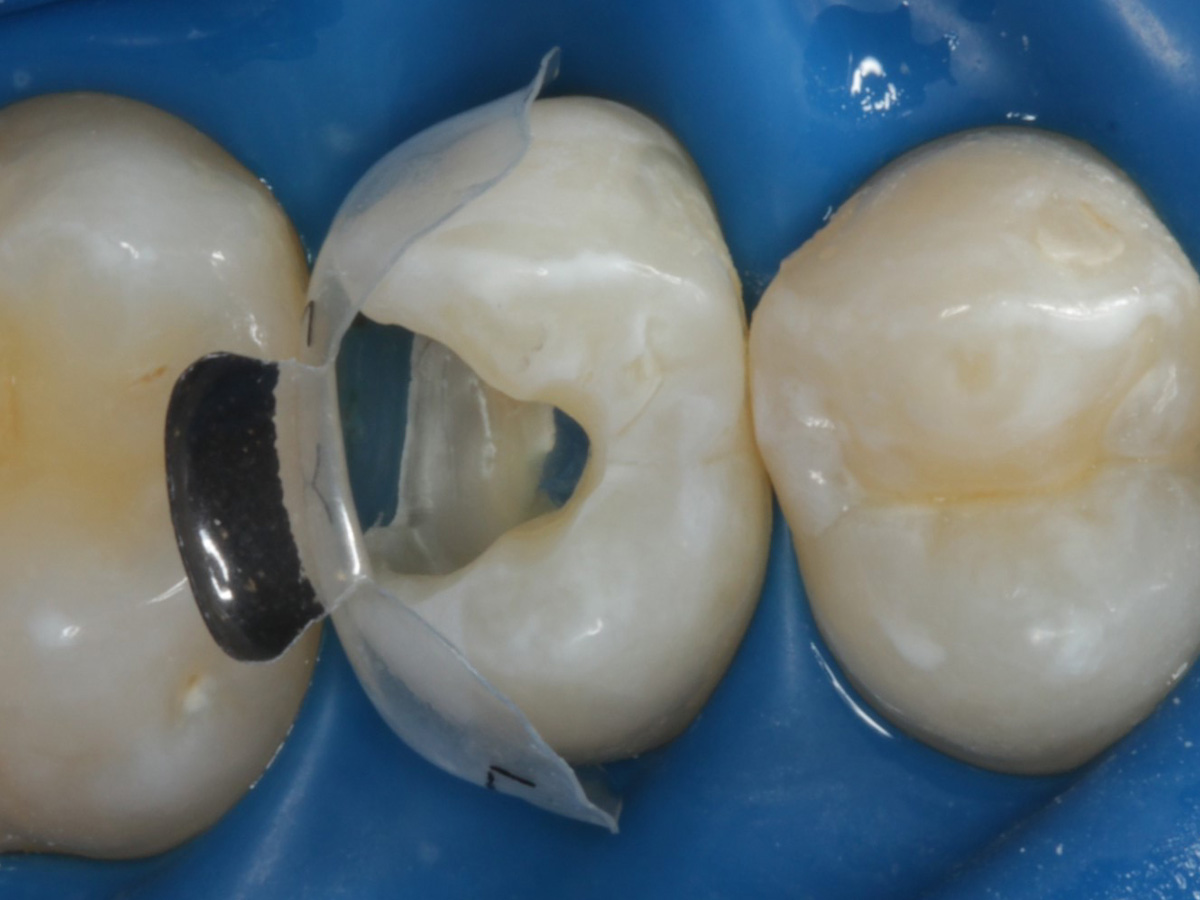

Abbildung 9

Nach Applikation der Matrize: Evolve Schwarz Prämolar- 7 mm; Schmelzätzung

Abbildung 10

Nach Spray und Trocknung der Kavität: perfekte Adaptation der Matrize insbesondere tief subgingival